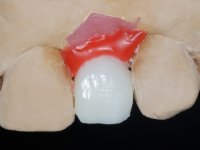

O tratamento iniciou-se com a re -preparação do coto do espigão falso coto fundido, com o objetivo de colocar as linhas de acabamento cervical com uma localização intra-sulcular e simultaneamente confecionar uma coroa provisória adaptada. Com um tratamento ortodôntico muito simples, fechou-se o diastema entre os incisivos centrais superiores e estabilizou-se esta posição com um arame colocado na superfície palatina dos centrais, funcionando como contenção. Posteriormente procurou-se fazer uma tração ortodôntica lenta do dente 2.2 com o intuito de diminuir, ainda que muito ligeiramente a perda óssea vertical nessa zona. Finalizada a tração, foi feita a extração do dente 2.2 e a zona foi reabilitada provisoriamente com uma coroa de resina composta colada aos dentes adjacentes. Foi colocado um implante dentário na zona do dente 2.2 sendo novamente colada a coroa provisória em resina, reabilitando provisoriamente a paciente durante o período de osseointegração. No dente 1.3 foi feita uma gengivectomia com bisturi elétrico, com a intenção de subir o nível cervical do 1.3 conseguindo uma maior harmonia com o dente 2.3. Estabilizados os tecidos moles, foi feita uma impressão com a técnica de moldeira aberta, utilizando silicones de adição de consistência “putty” e “light”. A recolha da cor, tanto da componente dentária como dos tecidos moles foi feita pelo ceramista no consultório.  No laboratório as impressões foram passadas a gesso e deram origem a modelos de trabalho que foram devidamente analisados. Foi decidido confecionar um “abutment” metalo-cerâmico aparafusado sobre o implante. Este “abutment” foi fundido com uma liga nobre e posteriormente revestido a cerâmica coronária e gengival. Dada a inclinação do implante o aparafusamento condicionou de forma inevitável a saída do orifício do parafuso pela superfície vestibular. No sentido de esconder esta situação, o desenho do “abutment” já foi idealizado com a intenção de acomodar na superfície vestibular a colagem de uma faceta feldspática. Este “abutment” foi provado em boca e foram feitos ajustes no componente cerâmico gengival. A sua adaptação aos tecidos moles foi feita tanto de forma subtrativa, com broca, como de forma aditiva, acrescentando resina composta de tonalidade gengival. Este acrescento de resina seria orientador do ceramista na colocação final da cerâmica de tonalidade gengival. A coroa que reabilitaria o dente 1.3 foi cimentada nesta consulta de prova com cimento de ionómero de vidro reforçado com resina composta. Finalizado o trabalho em laboratório da faceta sobre o 1.2 e o “abutment” e a faceta para o implante este foi colado em boca, após a colocação do isolamento absoluto. O trabalho satisfez plenamente a paciente. Durante oito anos a paciente foi seguida regularmente, mostrando-se agradada com o tratamento efetuado, no entanto começou a mostrar interesse em intervir esteticamente nos incisivos centrais superiores. Decidida a segunda fase da nossa intervenção, foi feita a preparação dentária dos dentes 1.1 e 2.1 para a colocação de duas facetas feldspáticas. Particular cuidado foi tido na preparação inter-proximal distal junto ao “abutment” do implante. Foi preciso avaliar muito pormenorizadamente o eixo de inserção da faceta em relação ao “abutment”. As facetas feldspáticas foram confecionadas em laboratório e posteriormente coladas em boca após a colocação de isolamento absoluto. Um ano após, iniciamos a nossa terceira fase de tratamento, após a faceta colada no dente 2.1 ter fraturado. A preparação dentária foi feita sobre a faceta colada, procurando estender mais para palatino o interface inter-proximal distal. O objetivo seria passar para mais palatino do ponto de contacto o interface faceta-dente. O preparo dentário do dente 1.2 também foi muito reduzido, limitando-se a criar um eixo de inserção. Após confecionadas a coroa total e a faceta em laboratório foram coladas em boca. Primeiro foi colada a coroa utilizando-se um isolamento relativo com teflon, posteriormente foi colada a faceta após a colocação do isolamento absoluto. Na coroa utilizei este tipo de isolamento para evitar a utilização de grampos. Seria difícil de aplicar pela forma e dimensão do dente e agressivo para os tecidos moles. Após a colagem foi avaliada a integração oclusal do trabalho.